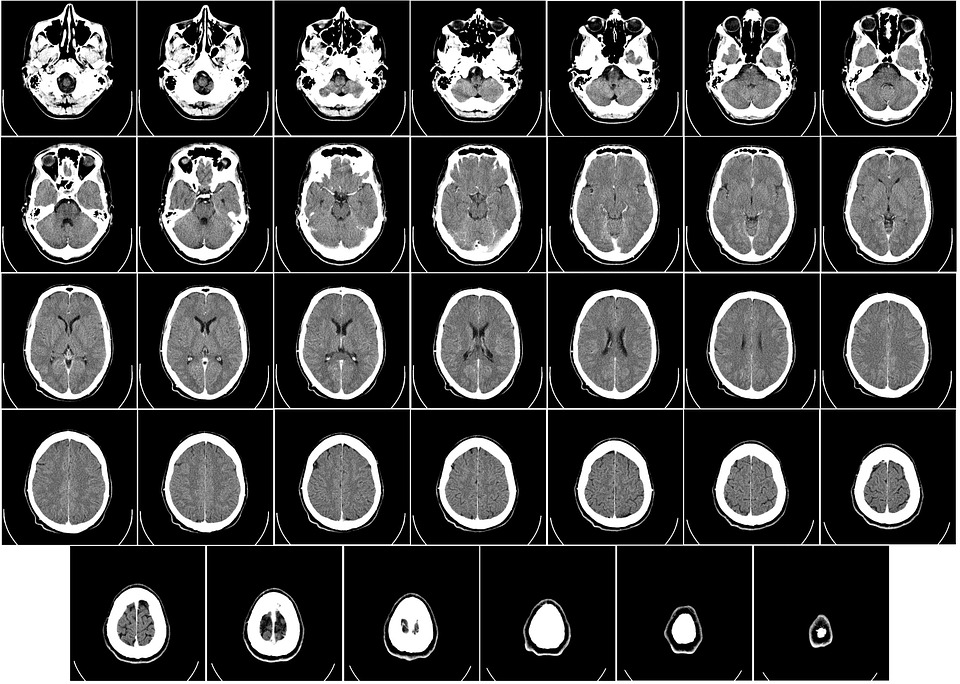

흔히 불안장애와 스트레스장애는 전반에 걸쳐 정신건강 진단 중에 30%를 차지한다. 초기에는 이 두 장애를 뇌의 결함으로 인한 질환으로 판단했지만 뇌를 스캔할 수 있는 영상기술이 발전하면서 뇌의 신경회로에 대해 면밀한 연구가 가능해질 것으로 내다보고 있다.